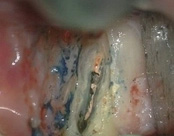

The patient was eating and bit down, felt and heard a “pop.” The tooth had cracked in the middle of the root. The tooth helps hold the patients partial in place and did not want to lose the tooth. The crack was removed with the laser and then restored.

The photograph is 2 months after the crack repair. The area looks like nothing was done (no redness, no scarring, etc.) and the tooth is there helping to hold the partial denture.